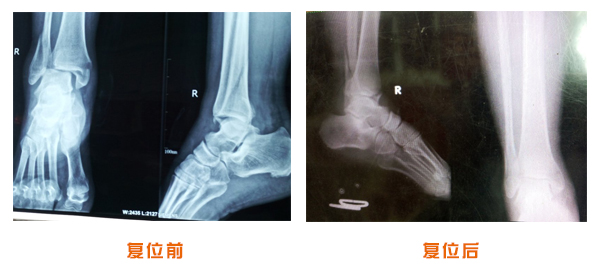

肥城市安駕莊梁氏骨科醫(yī)院是一所以梁氏手法正骨配合膏藥為特色的現(xiàn)代化專科醫(yī)院。

梁氏骨科術(shù)始創(chuàng)于清雍正年間,歷經(jīng)八代,至今已有三百年歷史。據(jù)1929年泰安縣志載“梁瑞圖先生,字增生,號蓮峰,安駕莊人,精岐黃并發(fā)明接骨,凡跌打車凡跌打車軋皮不破而碎骨者......【詳細】 |